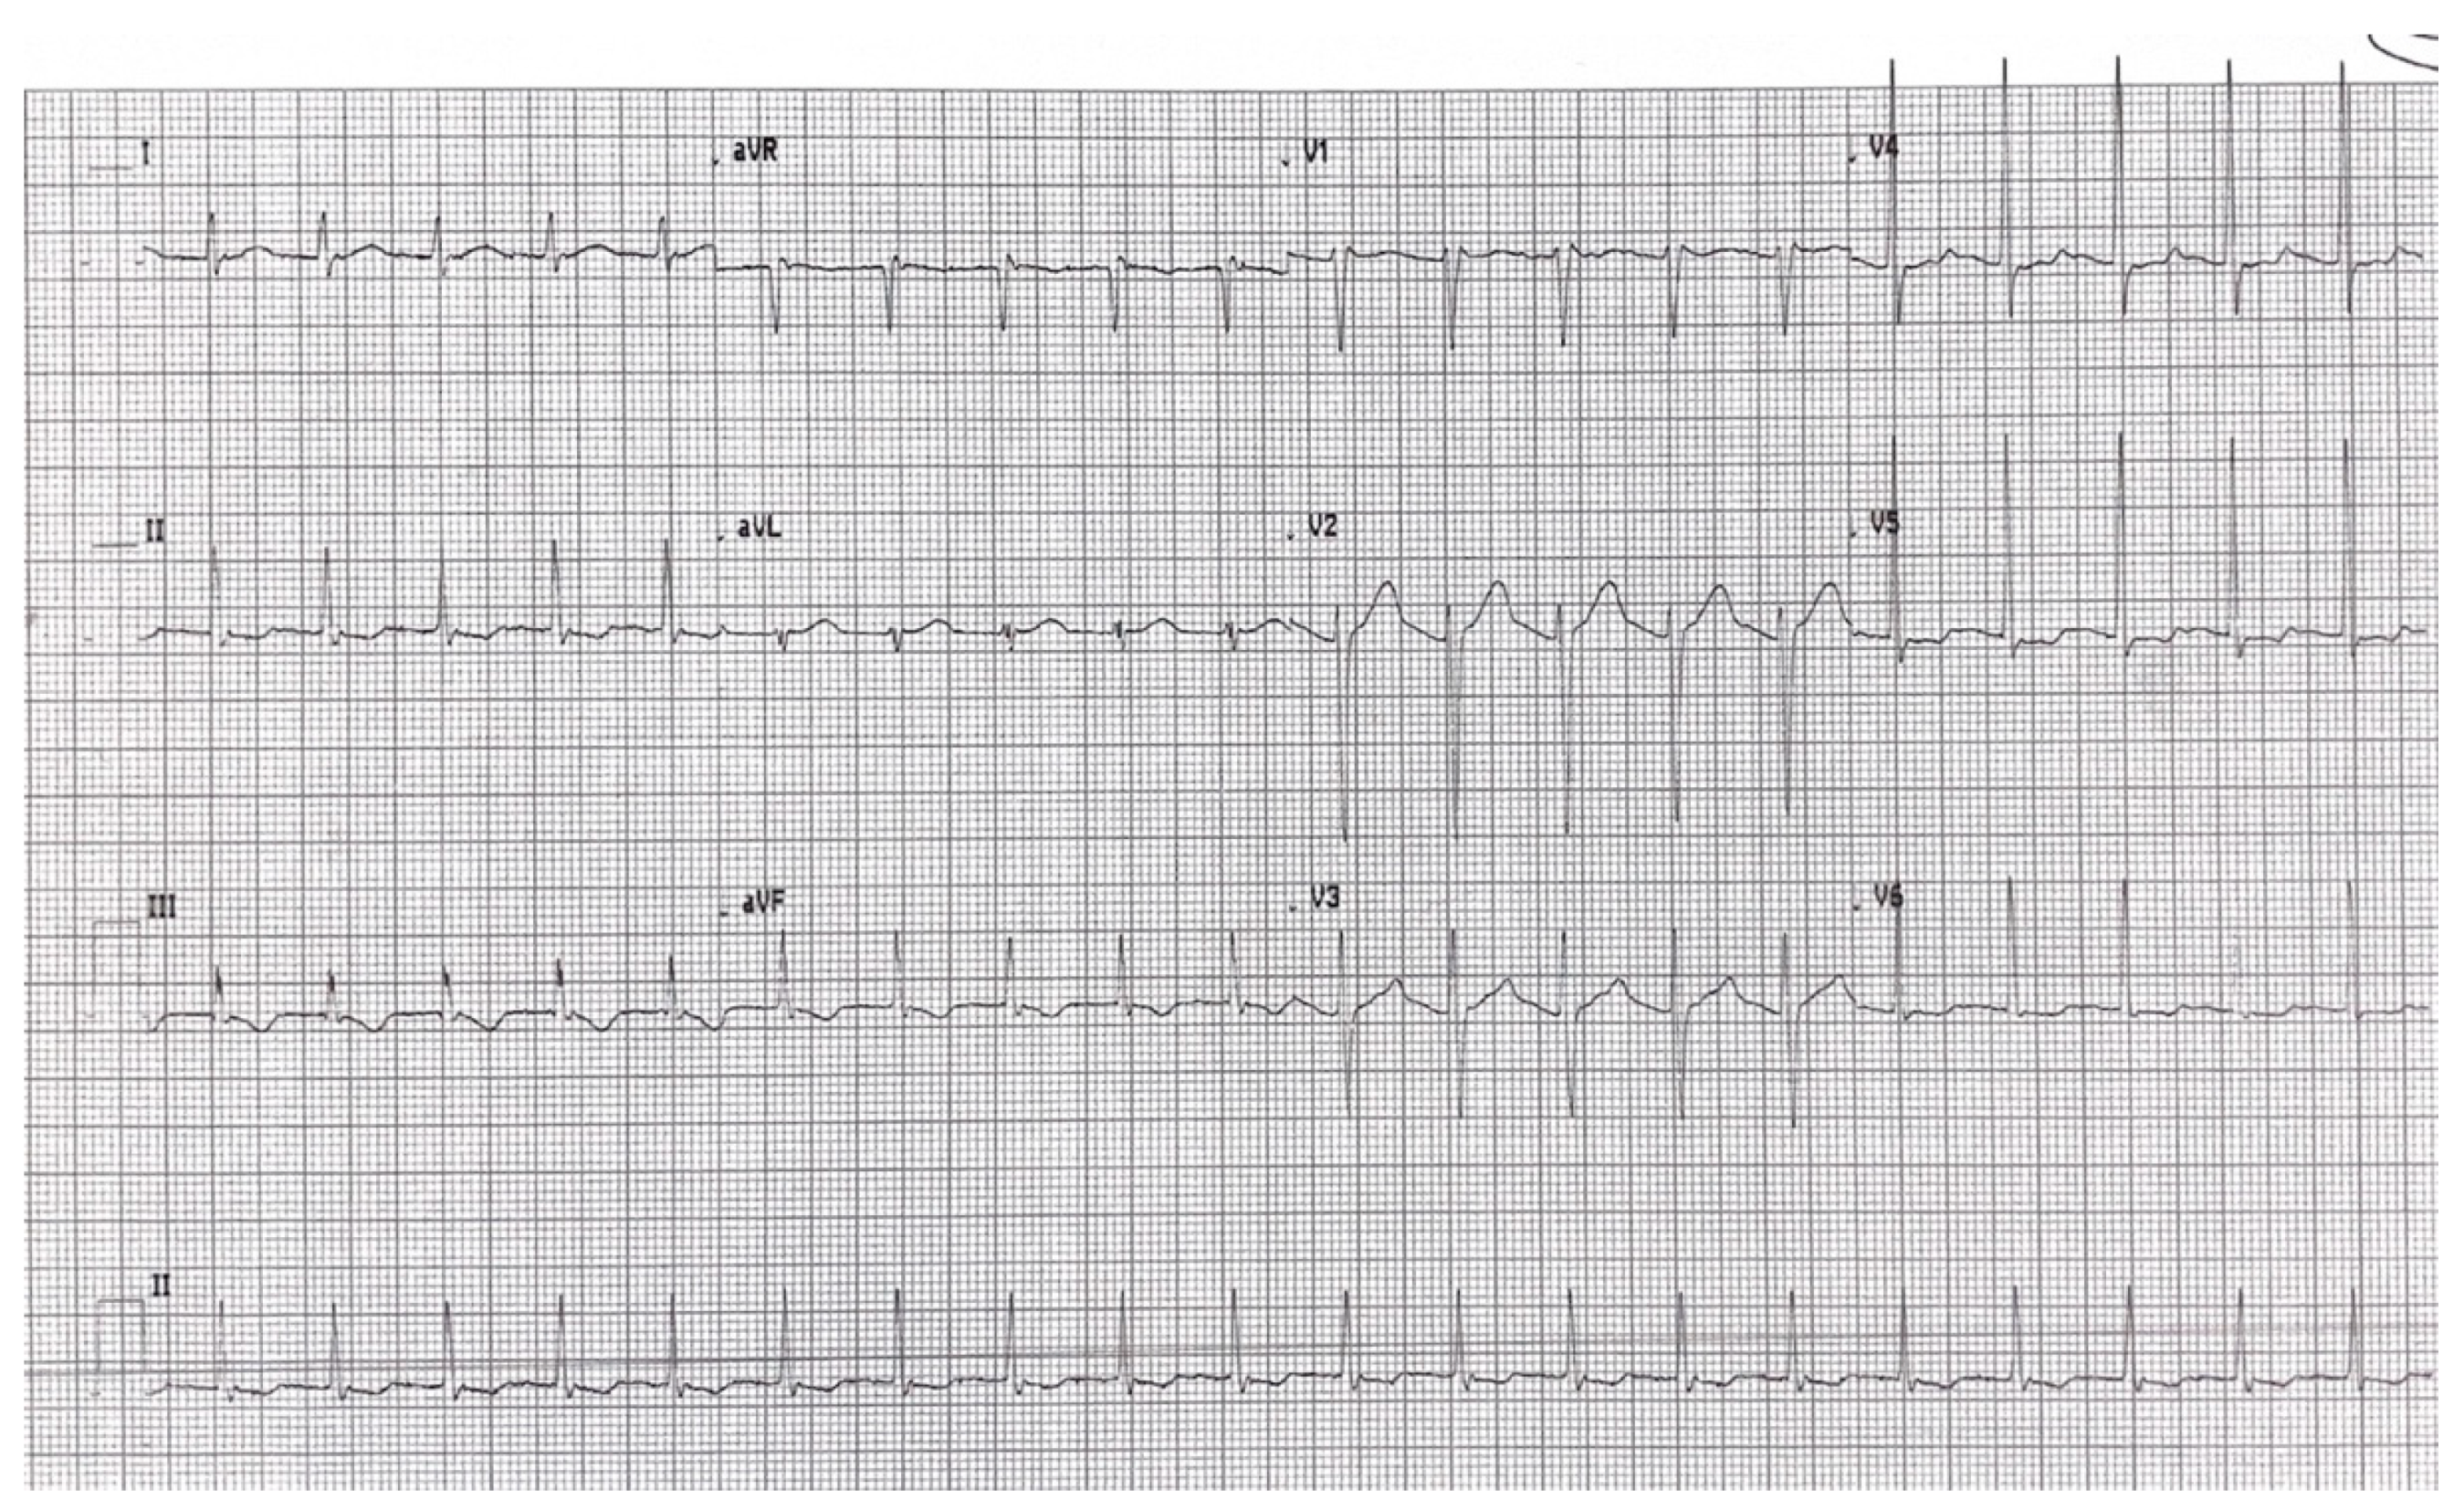

2. Detailed Case Description